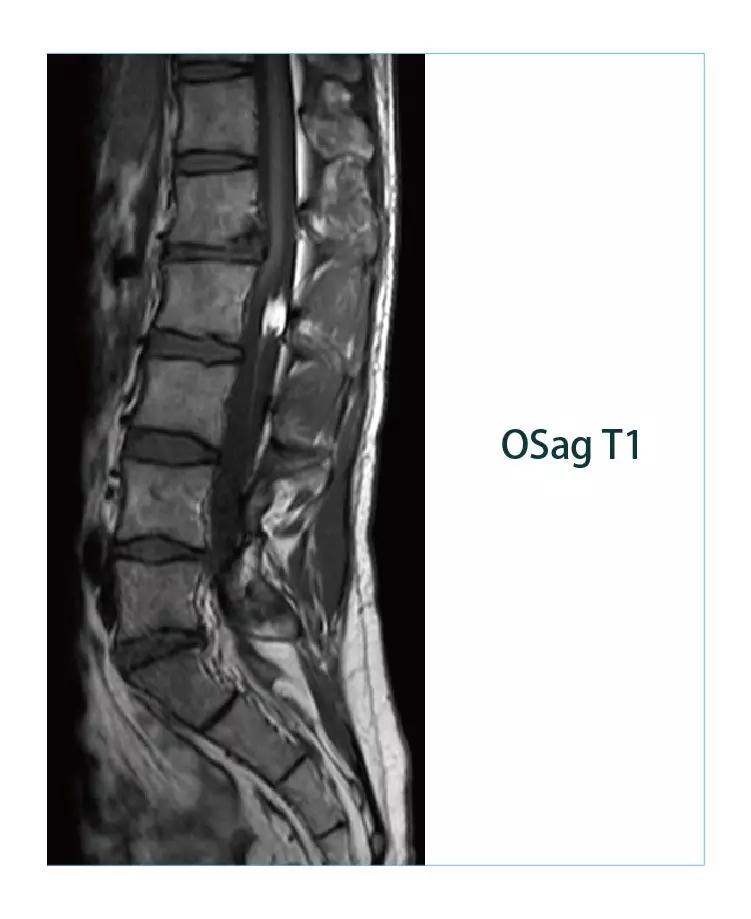

【朗润影像档案】20190225磁共振影像病例结果讨论